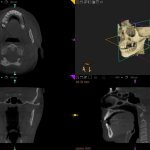

Eine 3D CT-Aufnahme besteht aus mehreren hundert 2D-Bildern, die digital übereinandergelegt und zu einem ‚durchfahrbaren‘ 3D-Modell des Schädels zusammengesetzt werden. Sie lässt sowohl Höhe, Dicke und Breite von Kieferknochen und Zähnen erkennen, als auch – wenn auch etwas weniger präzise als die herkömmliche CT – Weichgewebe und Nervenkanäle. Zudem ermöglicht das 3D CT die Messung der Knochendichte.

Durch die 3D-CT-Diagnostik ist es möglich, auch exakte Messungen bezüglich der Knochenbreite und Knochendichte vorzunehmen, in Problemfällen Wölbungen und Knochenhöhlen auf einzelnen Schichtaufnahmen erkennbar zu machen, sowie die Position und den Verlauf der Nervenbahnen zu veranschaulichen. Man erhält eine überlagerungsfreie Darstellung und sieht alles Verborgene, was bei der Planung von implantologischen Eingriffen enorm wichtig ist.